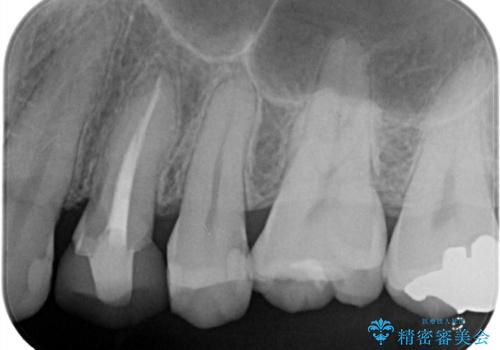

- 定期健診にて虫歯が見つかった患者さんです。他院で保険治療(CR、プラスチック)したところとまだ処置されていないところが虫歯になっていました。

セラミックインレーで治療しました。

以前保険治療で治したところが再び虫歯になっていました。保険治療で使用される材料は主にプラスチックなので必ず劣化がおきます。再治療のリスクを減らすために、セラッミックインレーで治療を行いました。セラミックインレーには劣化がほとんどありません。当院ではシリコンで型取りを行っているので、適合が良い被せものが出来き再治療のリスクを減らすことが出来ます。